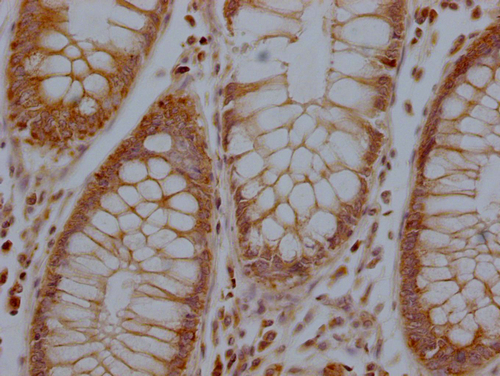

IHC image of CSB-PA744137LA01HU diluted at 1:100 and staining in paraffin-embedded human colon cancer performed on a Leica BondTM system. After dewaxing and hydration, antigen retrieval was mediated by high pressure in a citrate buffer (pH 6.0). Section was blocked with 10% normal goat serum 30min at RT. Then primary antibody (1% BSA) was incubated at 4°C overnight. The primary is detected by a Goat anti-rabbit polymer IgG labeled by HRP and visualized using 0.05% DAB.